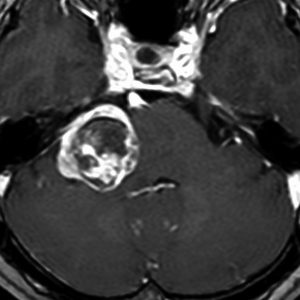

定位分割放射線治療をした聴神経腫瘍の例(左)。20%くらいの確率で放射線治療後に一時的に大きくなることがあります(中央)。やがて小さくなっていきます(右)。放射線治療後に腫瘍が大きくなっても,あわてて手術を受け入れてはいけません。

この画像はMRIのCISS/FIESTA画像というのを用いています。造影剤を使わないでも腫瘍の形と大きさが精密に解るので,経過観察には適している検査法です。

2001年に治療をした,40代女性の大きな聴神経腫瘍です。50グレイ25分割の定位放射線治療を行いました。中央が1年後,右が3年後です。徐々に縮小して手術を必要としませんでした。このサイズの聴神経腫瘍でも放射線治療は選択できるのですが,多くの場合は開頭手術をお勧めするサイズとも言えます。